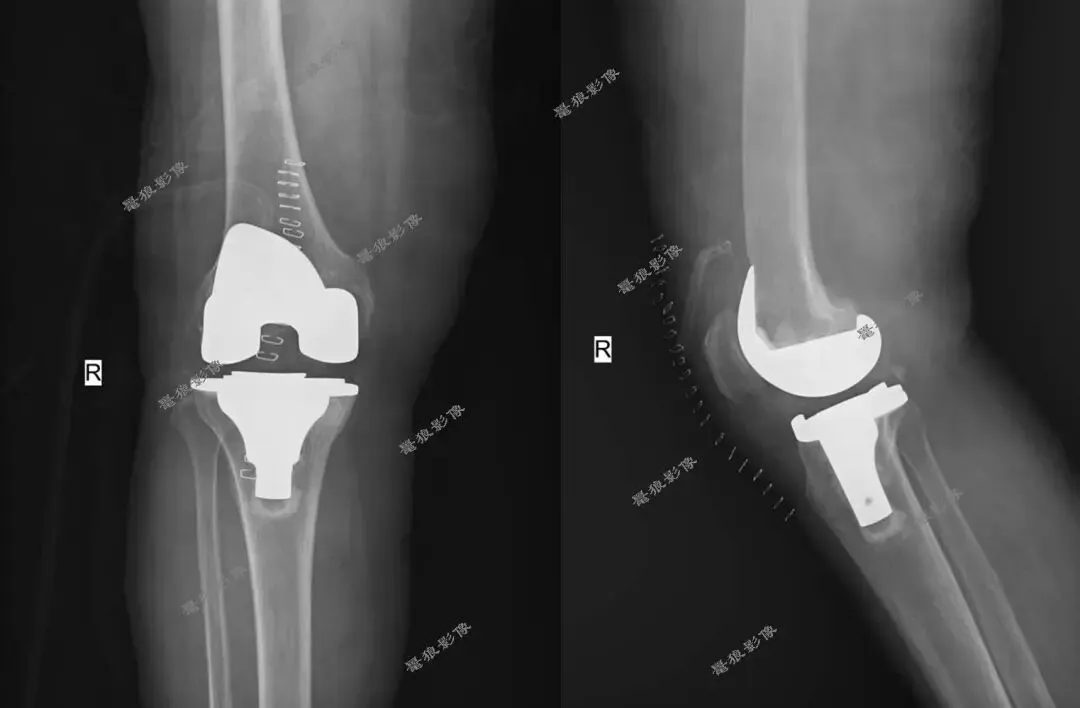

术后: